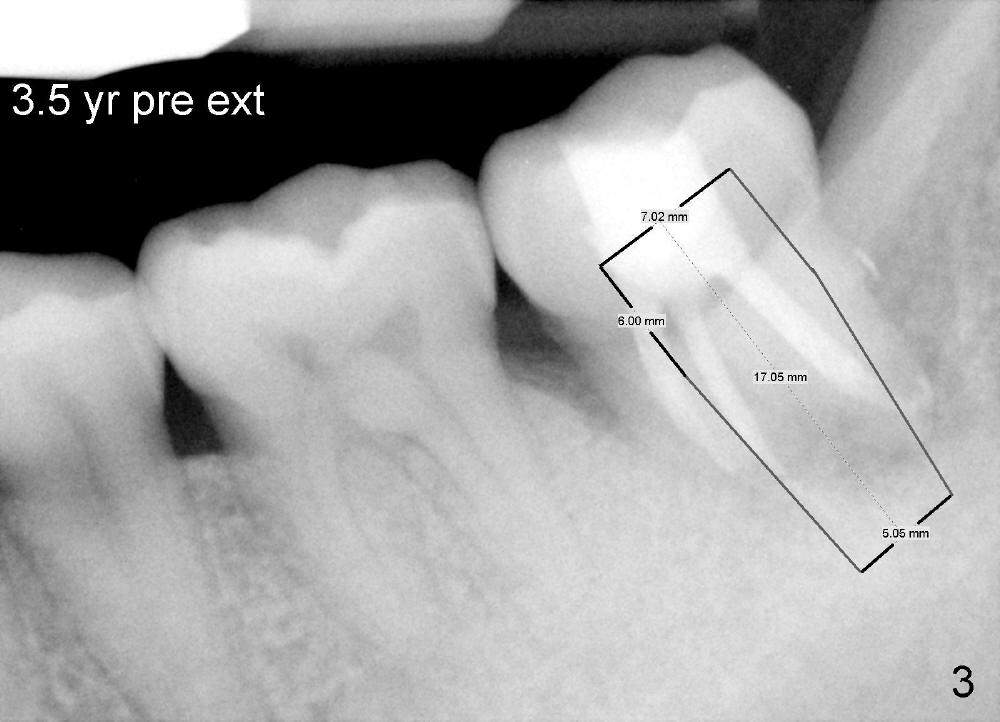

The lower left 2nd molar of a 45-year-old lady has perio-endo disease (Fig.1). The patient is not only very nervous, but also active in gag reflex. It is difficult to take good preop PA (Fig.1 *: ). Root canal therapy is performed. A relatively good PA is taken 1 year postop, again due to gap reflex (Fig.2). The tooth is still nonsalvageable (Fig.3). The last PA is taken 3.5 years before extraction and immediate implant. Infiltration anesthesia is administrated first. The patient experiences pain during early stage of osteotomy, but she does not report readily. Block anesthesia is added. Intraop PAs are taken with difficulty (Fig.4,5 with #1 sensor; 5 mm tap in place). Invasion of the inferior alveolar canal is not noted (Fig.5 dashed line). Oozing is a little more than expected. This is ignored. A 7x14 mm tapered implant is placed; the upper border of the inferior alveolar canal is not intact (Fig.6). Paresthesia area is defined next day (Fig.7). The implant is reversed for a few turns. Paresthesia area is reduced 19 days later (Fig.8). The implant is not stable. Follow up PAs are taken with difficulty (Fig.9-11). It appears that a shorter cylindrical implant is more appropriate for this case (Fig.11). The implant is stabilized with splinting with questionable result (Fig.12).